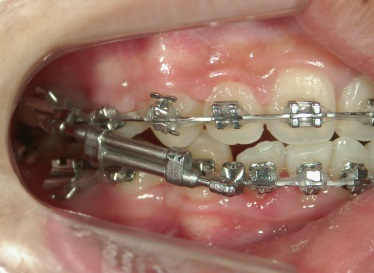

矯正歯科 治療途中 下顎の後退を改善する為、ツインフォースで下顎を前に出す

no.18_2196_治療中_右.jpgno.18_2196_治療中_正面.jpgno.18_2196_治療中_左.jpg